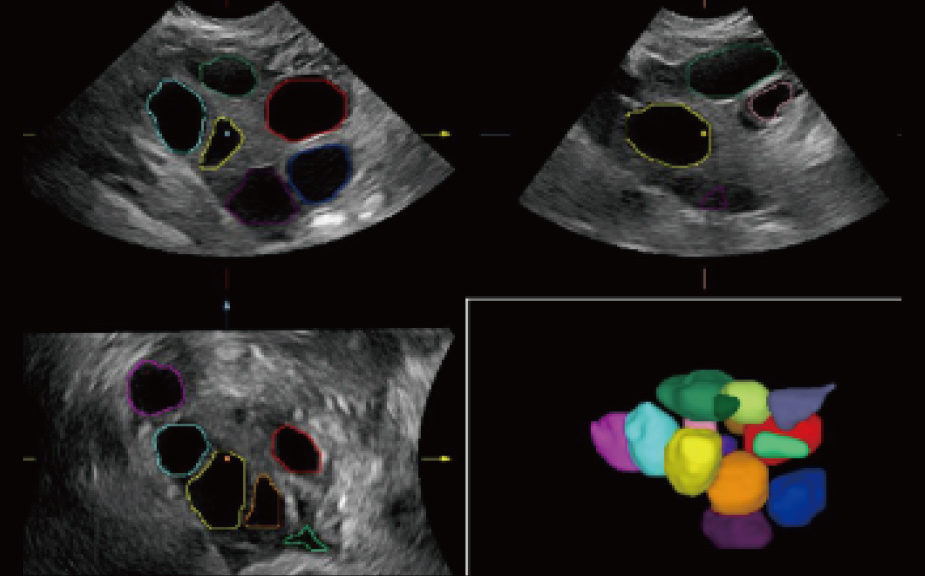

Scenario-oriented Full-stack Intelligence

The innovative Smart Scene 3D solution enables automated identification of tissue characteristics and delivers organ-specific diagnosis with full-stack intelligence throughout the entire procedure. This innovation reduces dependence on clinical skills, while elevating diagnostic accuracy, confidence, and efficiency.